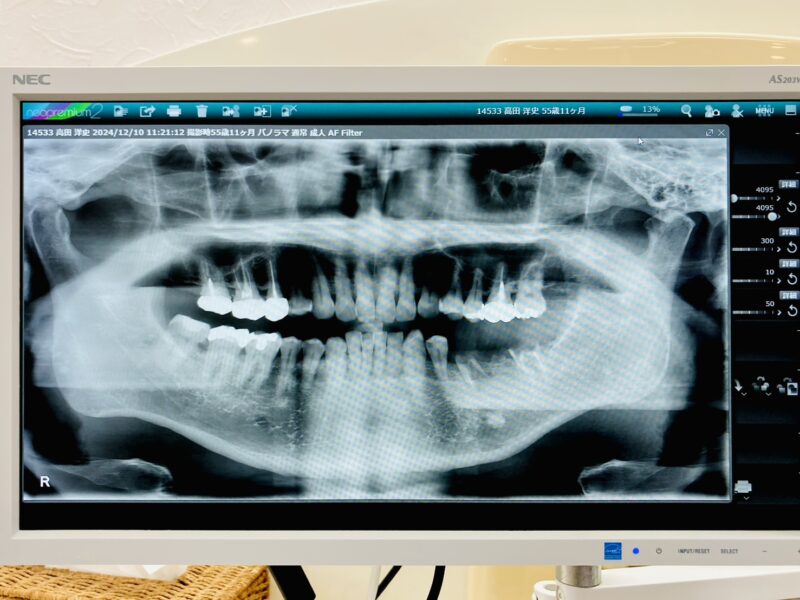

(画像右下)